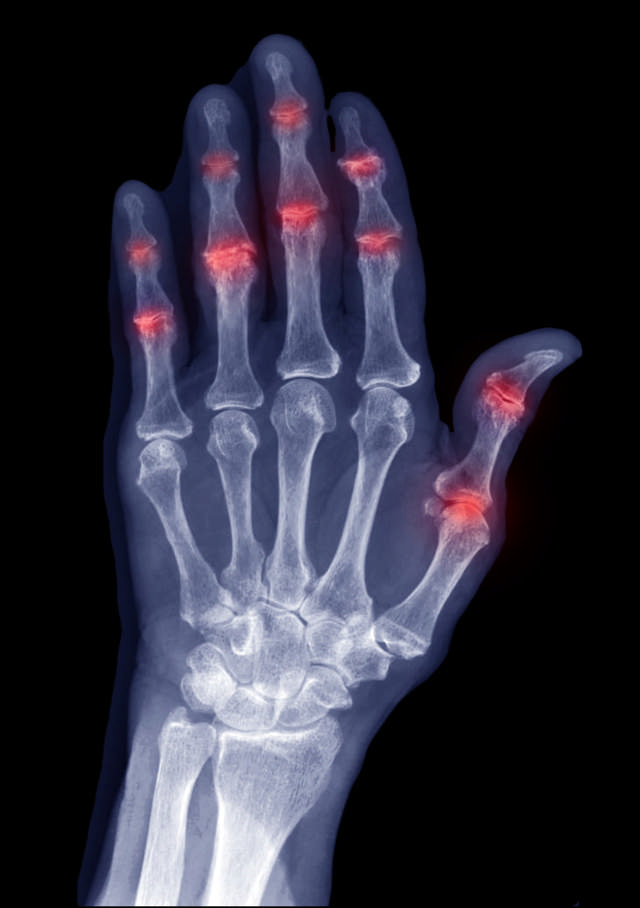

Ved PsA går kroppens immunsystem til angrep og skader enkelte av kroppens egne celler, for eksempel leddhinneceller. Dette kaller vi en autoimmun reaksjon. Den betente leddhinnen blir fortykket på grunn av økt cellevekst og opphopning av betennelsesceller, og kan da ødelegge brusk og benvev. Det skilles ut for mye leddvæske, og leddet kan bli rødt, varmt og hovent. Bevegeligheten i leddet kan bli sterkt redusert. Alt dette kan lede til store skader på leddet.

Bilde: Betennelse i fingerleddene (iStock).